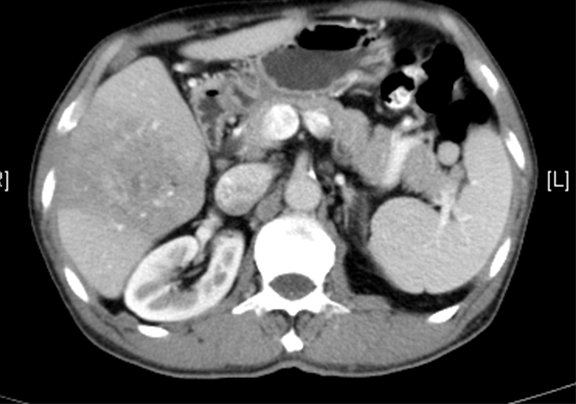

上腹部动态增强CT:1. 肝右叶占位性病变,考虑肝Ca 并肝右静脉瘤栓可能性大,请结合临床2. 副脾3. 肝内外胆管扩张,必要时MRCP检查4. 胰腺颈部小囊状低密度影,建议MRI 检查

通过调节窗宽窗位调整CT序号,对肿瘤,肝实质,胆囊,下腔静脉,肿瘤,肝动脉、门静脉及肝静脉等进行三维重建;系统自动计算肿瘤体积和肝脏体积。

模拟手术操作,自动计算切除肿瘤体积。肝脏体积为1058ml,肿瘤体积为562.1ml,肿瘤体积为肝脏体积的53.1%,通过比对60-70岁正常肝脏体积为1262.7±284.31 ml,通过术前模拟手术,精准判断切除后剩余肝脏体积能耐受,避免肝衰竭发生。

术前CT检查:

动脉期

静脉期

平衡期